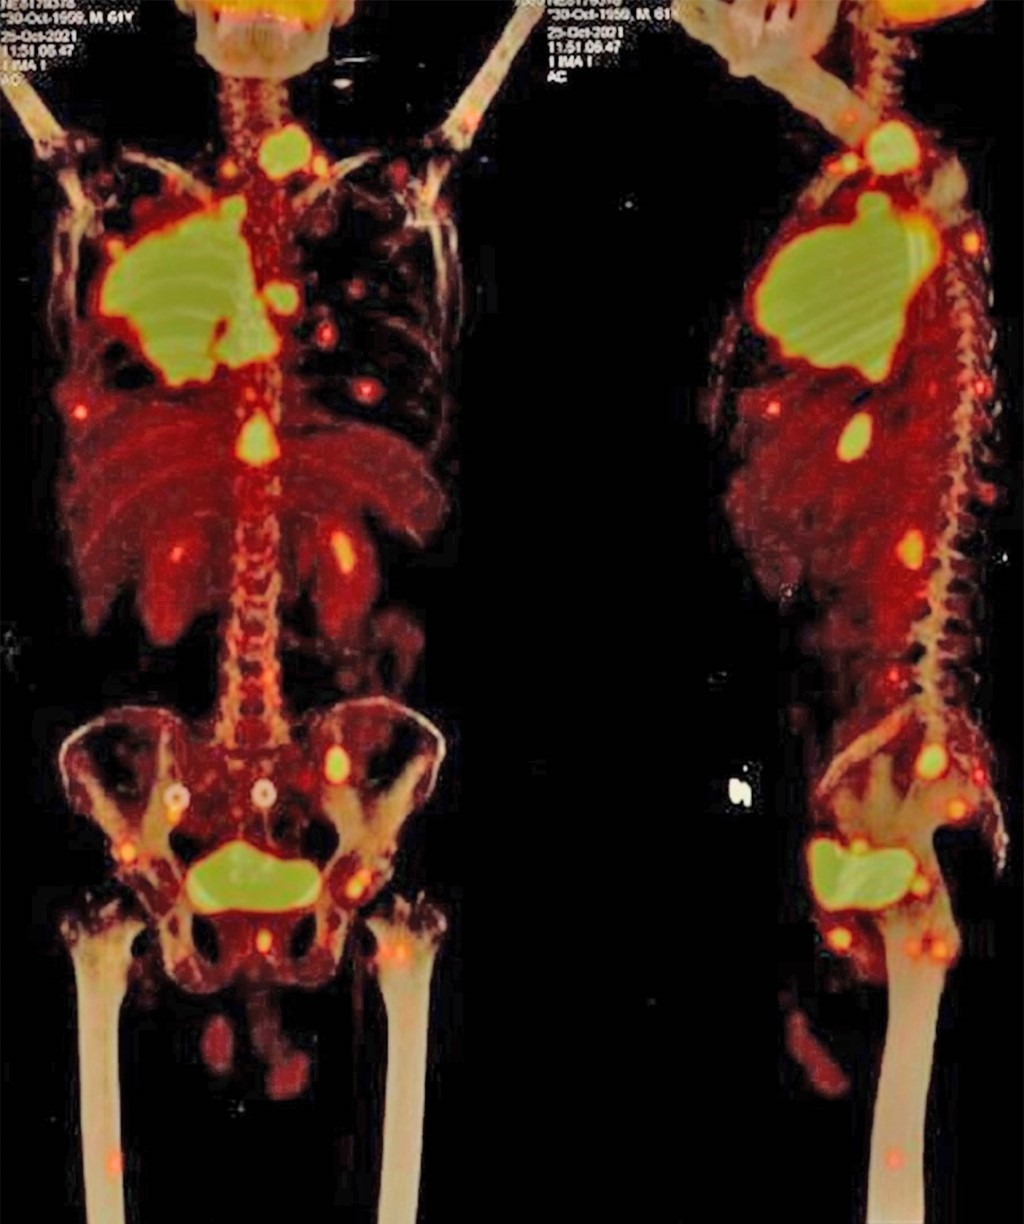

Introduction: genomic characterization is vital for the treatment and prognosis of non-small cell lung cancer (NSCLC) but can be challenging to interpret. Case presentation: a 62-year-old man with NSCLC adenocarcinoma had EGFR L861Q mutation, EGFR amplification, and MET amplification. Initial treatment with osimertinib resulted in mixed responses, with overall reduction but new hepatic lesions with PIK3CA and BRAF mutations. After CNS metastasis, the new profile again found mutations in EGFR and MET. Conclusions: genomic characterization is crucial for guiding treatment. New therapies promote tumor heterogeneity, so a multidisciplinary approach is necessary.

Figure 1